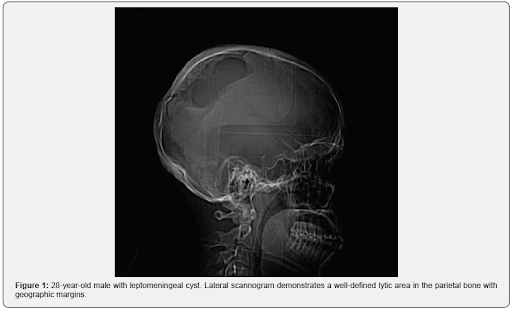

JUNIPER PUBLISHERS-OPEN ACCESS JOURNAL OF HEAD NECK & SPINE SURGERY Abstract Traumatic leptomeningeal cysts are a rare complication of a childhood skull fracture. Clinical manifestations of a childhood trauma are very rare in adults and usually presents as a nontender subcutaneous mass with progressive neurological deficit and seizures. Keywords: Leptomeningeal cyst; Adult; Trauma; Seizures; Skull fracture Abbrevations: CT: Computed Tomography; MRI: Magnetic Resonance Imaging; CSF: Cerebrospinal Fluid; T1WI: T1-Weighted Images; T2WI: T2-Weighted Images Case Report A 28-year-old male presenting with a gradually increasing scalp swelling in the left parietal region over a long period and seizures. The patient was conscious. On physical examination, there was a cystic swelling over the left parietal prominence. The swelling was compressible but non-tender and non-pulsatile. There was a history of head injury during infancy (Figure 1-5). A no...